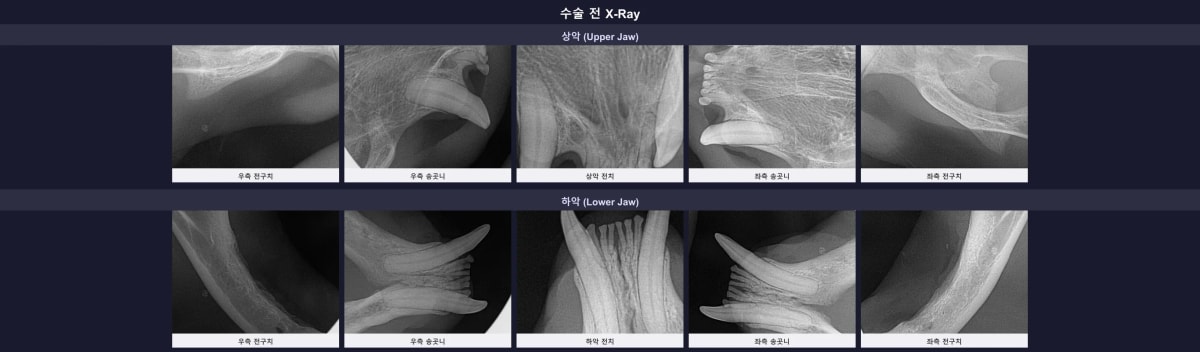

3. 수술 전 구강 엑스레이 평가

CT 검사와 함께 전체 치아에 대한 구강 방사선 촬영을 진행했습니다. 수술 전 엑스레이 사진을 살펴보니, 이미 많은 치아가 결손(MISSING) 상태였지만 남은 상악 앞니(103, 203) 주변으로 뼈가 녹아 치아 흔들림이 유발될 수 있는 소견이 관찰되었습니다. 반면 하악 앞니들은 가벼운 뼈 소실만 있어 면밀한 판단이 필요했습니다.

수술 전 진행된 겨울이의 구강 엑스레이 사진